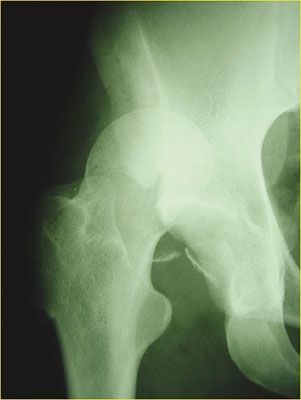

Mise au point Luxation de hanche sans fracture du cotyle associée : méta-analyses et série de cas rapportés , A. Meyer Clinique Paris V, 36 boulevard Saint-Marcel, 75005 Paris, France , G. Biette Hôpital de Meaux - 6 bis rue Saint-Fiacre - 77100 Meaux , Yves Catonné CHU de Fort-de-France, Service de chirurgie orthopédique et traumatologique, Quartier la Meynard, 97200 Fort-de-France, Martinique, France N°176 - Août 2008 ● 30 min de lecture